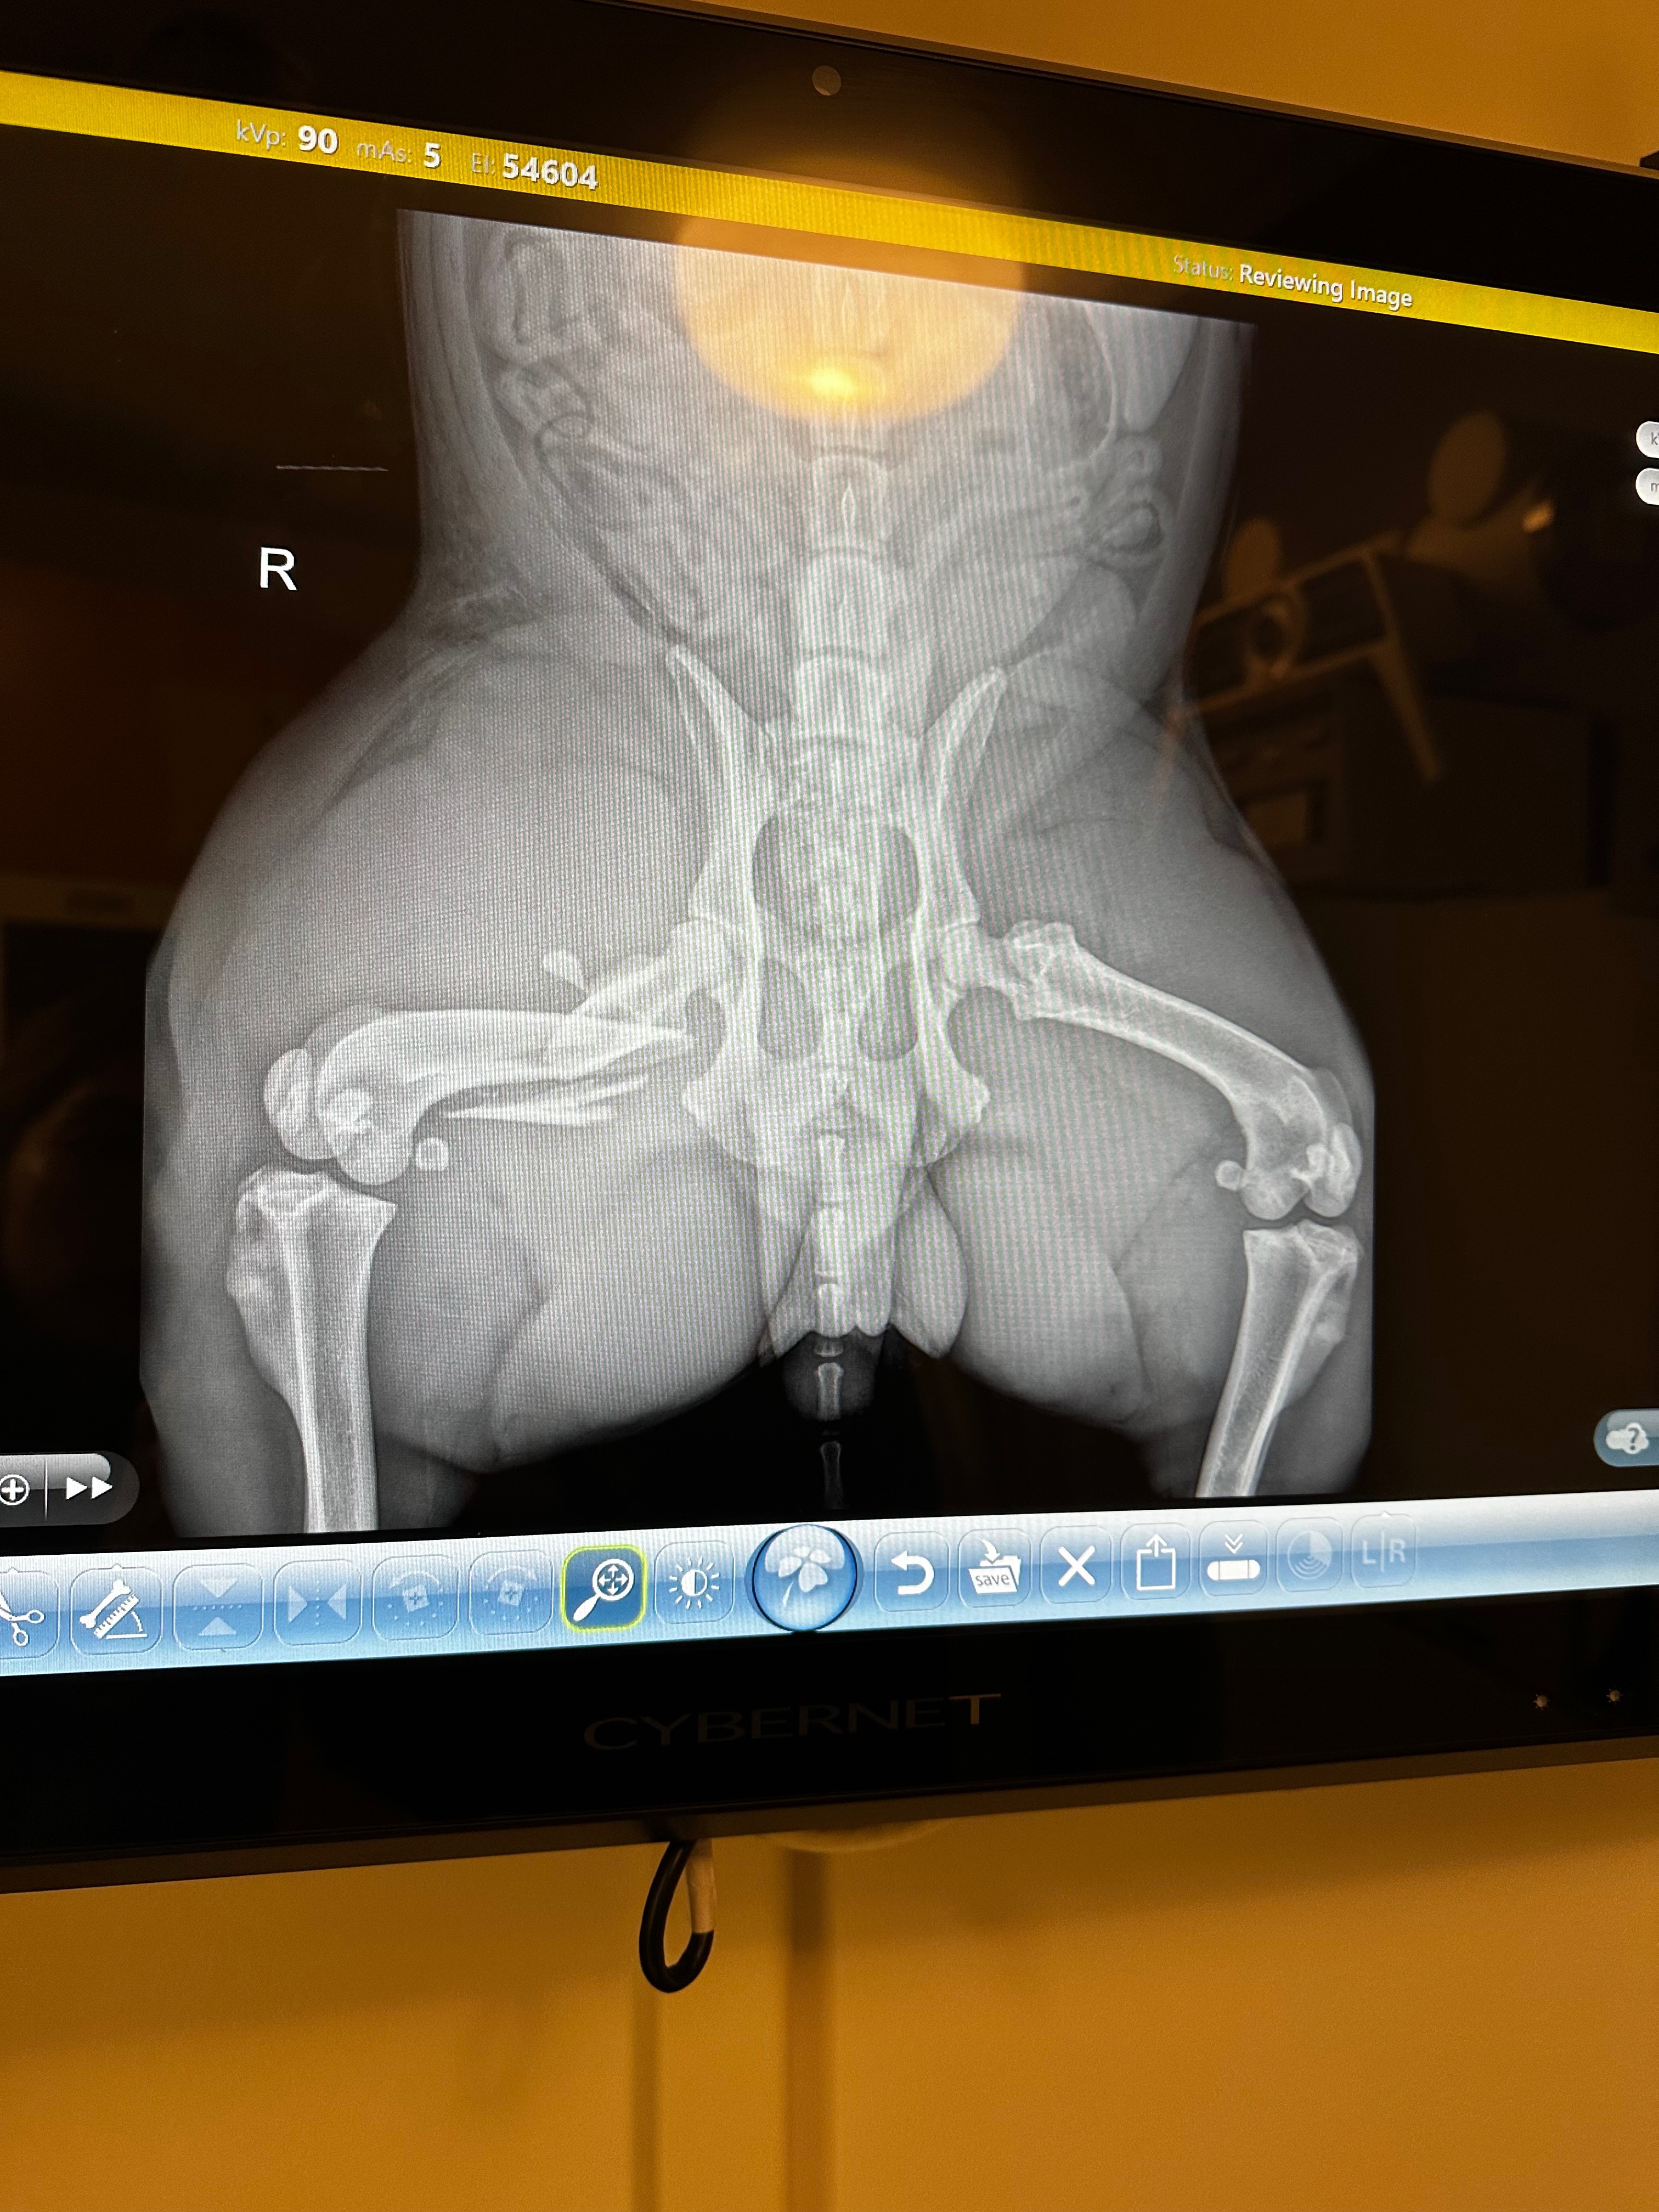

- Severe swelling to his right hind leg x-rays show fractured femur. unable to use leg at all due to the severity of his injury